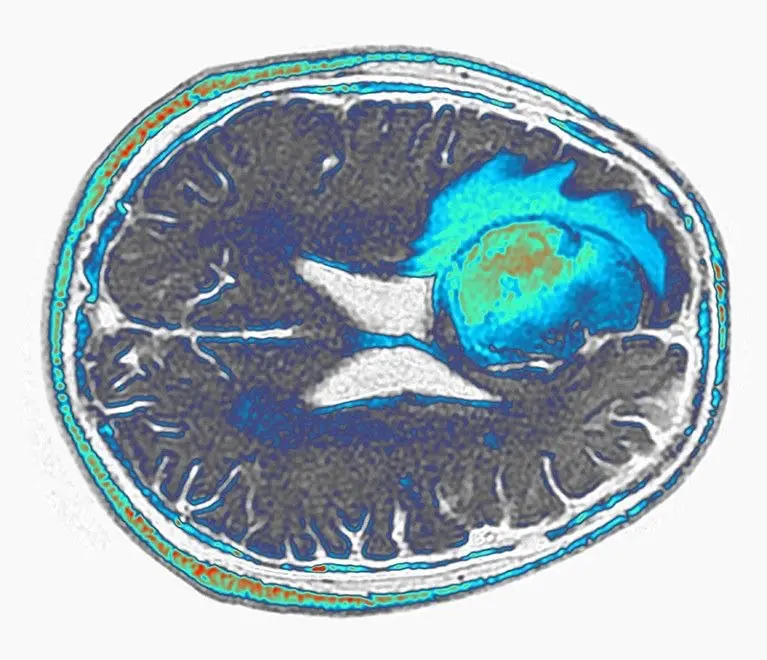

難治性脳腫瘍(膠芽腫・グリオブラストーマ)に対する免疫細胞療法(CAR-T療法)②

難治性脳腫瘍(膠芽腫・グリオブラストーマ)に対する免疫細胞療法(CAR-T療法)